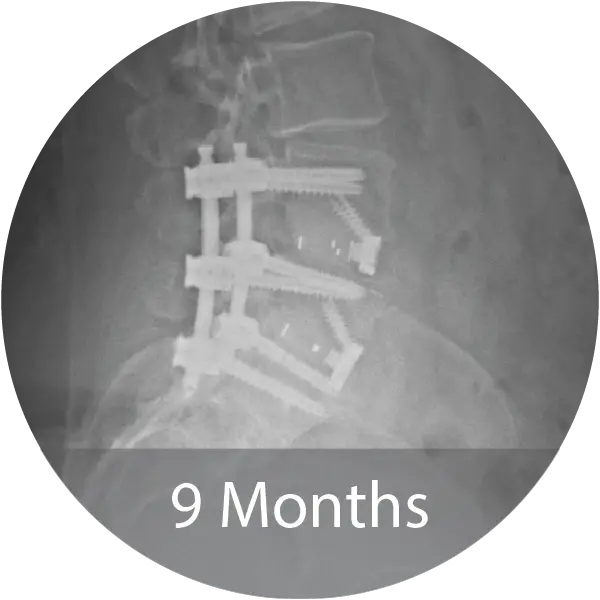

Two case series including a lumbar case (59-year-old female, 1 pack/day smoker) treated with L4–S1 ALIF with posterior fixation and a cervical case (60-year-old female, 1.5 pack/day smoker) treated with 3-level ACDF demonstrated solid arthrodesis by 9 months, significant improvements in pain and disability scores, no complications, and return to work. A cost analysis showed a 26–29% reduction in biologic cost per case when transitioning from INFUSE® and i-FACTOR® to NMP® Bioimplant, translating to an estimated annual savings exceeding $270,000 for the facility.